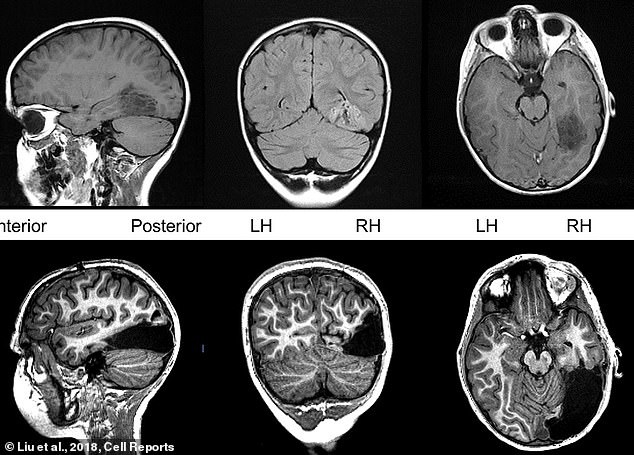

Mọi loại thuốc đều thất bại với Tanner. Phẫu thuật có thể ngăn chặn các cơn động kinh, nhưng nó sẽ phải loại bỏ một phần não bộ chịu trách nhiệm nhìn và xử lý thông tin hình ảnh. Các bác sĩ phải loại bỏ tất cả thùy chẩm phải, một nửa thùy chẩm phần hướng về phía sau, sát cổ.

Nhưng hiện tại, Tanner là một cờ thủ lành nghề. Mặc dù mất 15% bộ não, phần não bên trái của Tanner đã đảm nhận nhiệm vụ mà phần bên phải bị mất đã làm. Hiệu ứng này giúp cậu bé nhận diện được khuôn mặt và vật thể ở phía bên trái tầm nhìn.

Kể từ khi Tanner tỉnh dậy sau phẫu thuật, các bác sĩ đã theo dõi chặt chẽ cậu bé với sự hỗ trợ của máy cộng hưởng từ chức năng fMRI. Trong vòng 3 năm, Tanner cũng thường được cho làm các bài kiểm tra thị giác và hành vi, để so sánh với những đứa trẻ khỏe mạnh khác ở cùng độ tuổi. Cậu bé có chỉ số IQ trung bình, kỹ năng nhận thức ngôn ngữ và thị giác của cậu phù hợp với lứa tuổi.